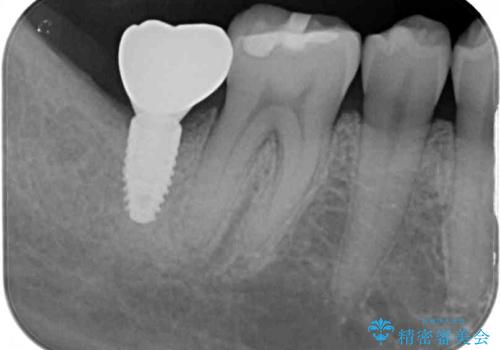

抜歯されたままの奥歯 ストローマンインプラントによる欠損補綴治療

- 抜歯してから放置されている右下の奥歯へのインプラント治療を希望して来院された患者様です。

世界中で高い信頼を得ているストローマンインプラントを用いて治療を行うこととしました。

ストローマン社のSLActiveというインプラントを使用し、インプラント埋入からクラウンが装着されるまで3ヶ月弱という短期間で終えることができました。